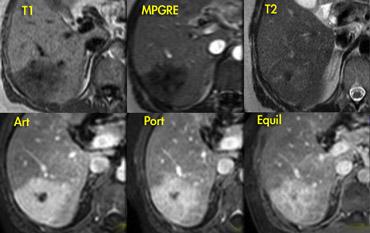

Bên trái là một FNH khác trên MR.

Tổn thương gần như đồng tín hiệu với gan trên chuỗi xung T1W và T2W, nhưng cho thấy tương phản rõ hơn với gan trên chuỗi xung T1W-MPRGRE (gradient-echo).

Ngấm thuốc trong pha động mạch có dạng thùy với các vách ngăn không ngấm thuốc, và trong pha cân bằng tổn thương không khác biệt so với nhu mô gan bình thường.

Lưu ý rằng tổn thương có một sẹo nhỏ.

Các FNH nhỏ thường không có sẹo trung tâm trên hình ảnh và thậm chí không có trên kiểm tra giải phẫu bệnh.